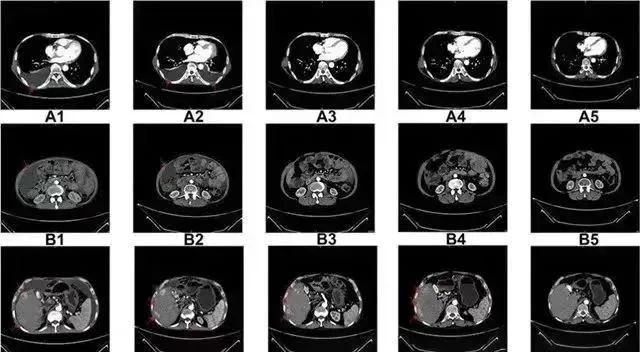

△ NK细胞治疗前和治疗期间的CT扫描结果

案例2:国内一名60岁的卵巢癌晚期患者,在接受了体外扩增,高度活化的同种异体NK细胞的治疗后,CA125水平从11,270降至580,所有腹水都消失了。此外,CT扫描的肿块体积减小,并且没有出现副作用。

案例3:一名广泛期小细胞肺癌患者,在进行4个疗程化疗和4次高度活化NK细胞回输后,患者第一次进行治疗后的CT复查,结果显示,肿瘤缩小到了原来的1/8。而且距发病第六年的CT复查中,仍旧没有发现任何异常及复发的迹象。